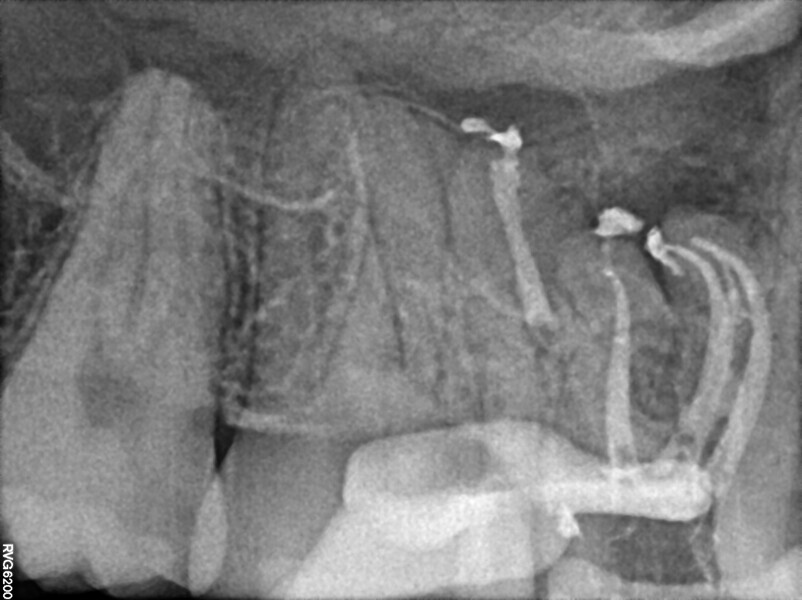

Post-op radiograph of a mandibular molar. (All Images: Bartłomiej Karaś)

A 25-year-old female patient presented to the office owing to constant pain related to the mandibular left first molar. Pulp necrosis was diagnosed. After the emergency appointment, the patient was referred for complete treatment. The tooth was treated in the same manner as described in the previous paragraphs. After creation of the access cavity, the orifices were located. In the root chamber, the orifices of the MB, mesiolingual, DB, distomesial and distolingual canals were present. After pre-flaring and preparation of the middle third, the LPE enhanced irrigation protocol with the SkyPulse laser was performed. After the irrigation protocol in the mesial root, the irrigants started to flow between lingual and buccal canals. Such an observation suggested to the operator that some space in the isthmus had been created. It is worth mentioning that at this stage apical enlargement was not performed. Final preparation of all five canals was performed with the reciprocating file, and the final irrigation protocol was performed as in the previous case. The radiograph clearly revealed that the isthmus space was filled with the sealer. The radiograph and CBCT image revealed that there were four portals of exit in the mesial root.